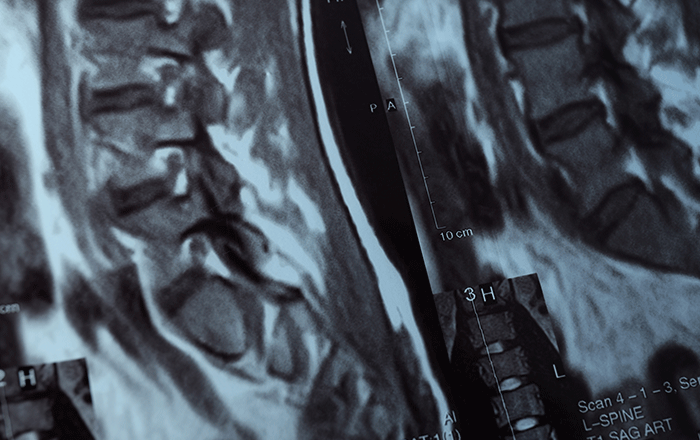

At Dr. Deborah Blades Neurosurgery, serving patients across Northeast Ohio, Percutaneous Kyphoplasty is a minimally invasive procedure designed to treat painful vertebral compression fractures, most commonly caused by osteoporosis, certain cancers, or trauma.

When a spinal vertebra collapses, it can lead to sudden, severe back pain, height loss, spinal curvature, and limited mobility. Kyphoplasty aims to stabilize the fracture, restore vertebral height when possible, and relieve pain so you can return to normal activities sooner.

During the procedure, a tiny incision is made and a narrow tube is guided into the fractured vertebra under X-ray guidance. A small balloon is gently inflated to create space and help restore height; the space is then filled with medical-grade bone cement that hardens quickly to stabilize the fracture. Most cases are performed as outpatient or with a short observation period.